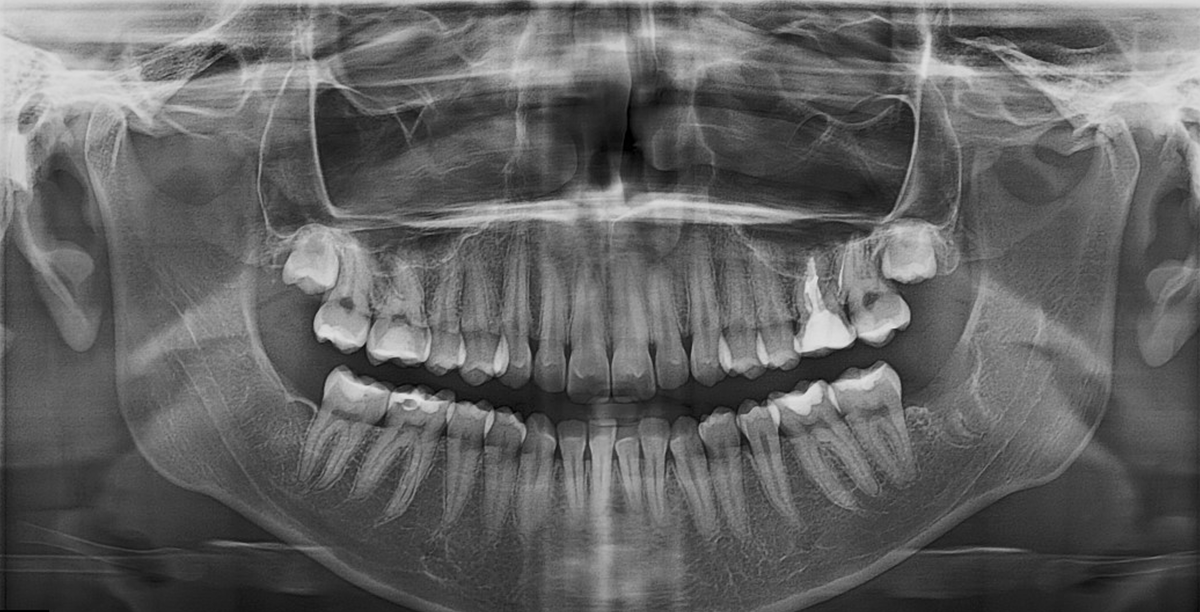

На данной панорамной томограмме зубных рядов визуализируем стандартную анатомию зуба 3.7.

Пациент женщина, 2003 г.р., зуб 3.7 анатомия